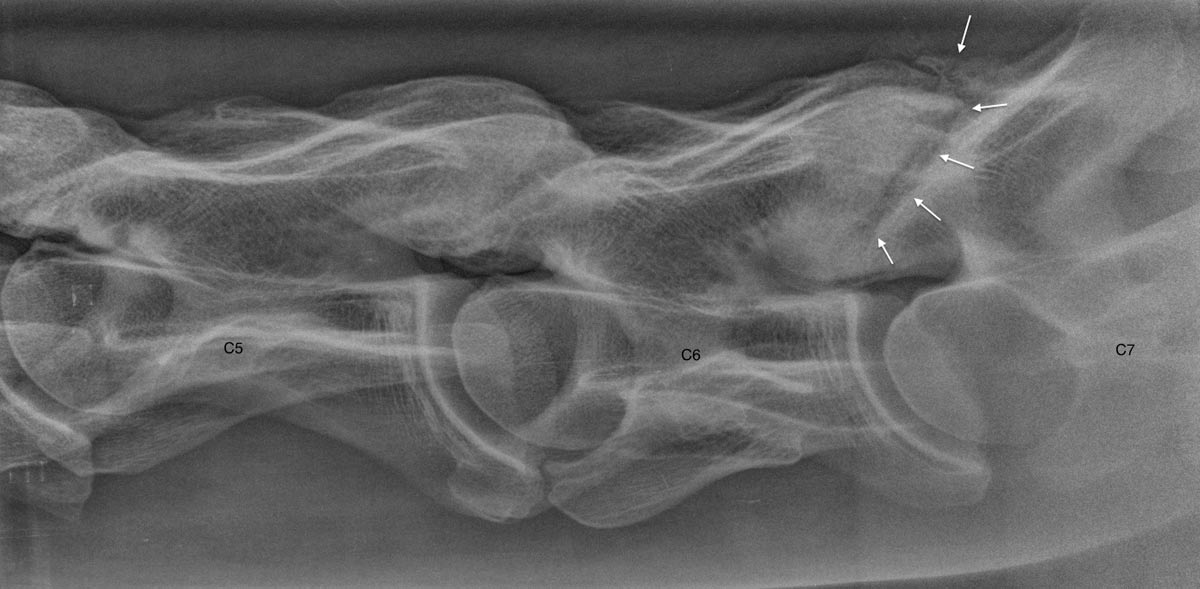

La radiographie est une technique ancienne qui connaît encore une grande évolution dans notre monde digital moderne. EquiSound dispose de 2 systèmes de radiographie digitale combinés à une machine à rayons X puissante de 80.000 Watts (80 kV). Nous pouvons produire des radiographies du cheval complet d’excellente qualité, tête, encolure et dos inclus.